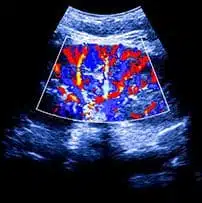

אקו לב עובר מתבצעת בדרך כלל על ידי קרדיולוג מומחה לילדים. הבדיקה דומה מאוד לאולטרסאונד רגיל שמבצעים בהריון, אך היא מתמקדת באופן מוגבר ובלעדי בלב העובר. ביצוע אקו לב בהריון מאפשר לרופאים שלכם לבחון מקרוב את מבנה ותפקוד הלב של ילדך שטרם נולד.

הבדיקה משתמשת בגלי קול ה"מהדהדים" בחלל הלב, ויוצרים תמונה של פנים הלב. תמונה זו מספקת מידע רב על התפתחות האיבר, מציגה את זרימת הדם דרכו ומסייעת לברר האם הוא פועל כראוי, האם קיימות מחלות לב או נדרש בירור נוסף.